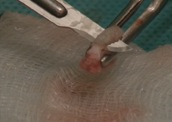

8. 16 h 35 : Préparation du greffon (suppression de l’épithélium).

9. 16 h 37 : Préparation du greffon et mise en forme du site.